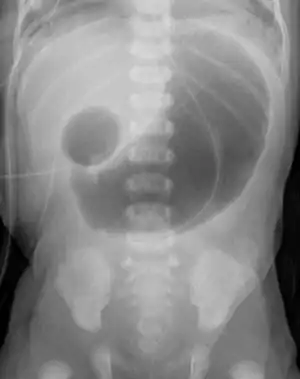

Double bubble (radiology)

In radiology, the double bubble sign is a feature of pediatric imaging seen on radiographs or prenatal ultrasound in which two air filled bubbles are seen in the abdomen, representing two discontiguous loops of bowel in a proximal, or 'high,' small bowel obstruction. The finding is typically pathologic, and implies either duodenal atresia, duodenal web, annular pancreas, or on occasion midgut volvulus, a distinction that requires close clinical correlation and, in most cases, surgical intervention.[1][2][3]